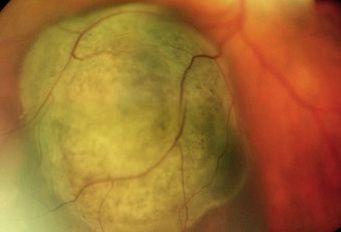

In der Aderhaut des Auges können Absiedlungen von Tumoren anderer Organe entstehen. Die Aderhautmetastase ist insgesamt der häufigste bösartige Tumor im Augeninneren. Beim Mann ist der häufigste zugrundeliegende Tumor das Lungenkarzinom, bei der Frau das Brustkarzinom. Es folgen Metastasen von Tumoren des Magen-Darm-Traktes, der Nieren oder von Karzinoiden. Die Metastasen im Augeninneren fallen dem Betroffenen erst bei Beeinträchtigung der Sehachse durch das Tumorgewebe oder die begleitende Flüssigkeitsansammlung unter der Netzhaut auf. Sie kommen in einem drittel der Fälle mehrfach in einem Auge vor und sind in einem drittel der Fälle in beiden Augen zu finden.

Aderhautmetastasen wachsen im Allgemeinen recht schnell, so dass sie auch einer zügigen Therapie zugeführt werden sollten. Die Behandlung erfolgt immer in Zusammenarbeit mit onkologisch und strahlentherapeutisch Betreuenden. Die Therapie des zugrundeliegenden Tumors kann eventuell schon zur Rückbildung der Aderhautmetastasen führen. Die fraktionierte externe Bestrahlung führt in den meisten Fällen zu einer guten Regression der Metastasen.